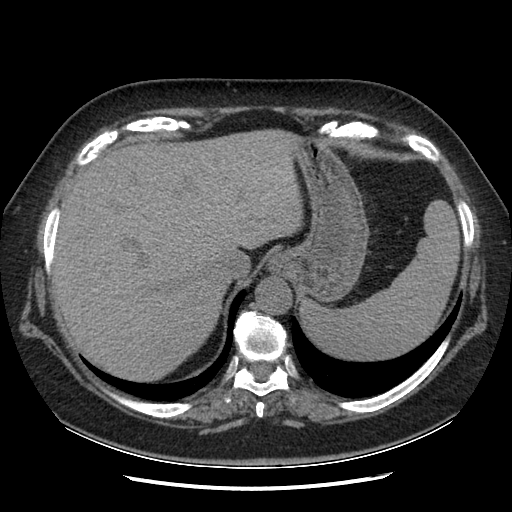

Original VENOUS CT scan

No window - Raw intensity values

Lung window (WL -600, WW 1500 β†’ Low βˆ’1350, High +150)

Mediastinum window (WL 40, WW 400 β†’ Low βˆ’160, High +240)